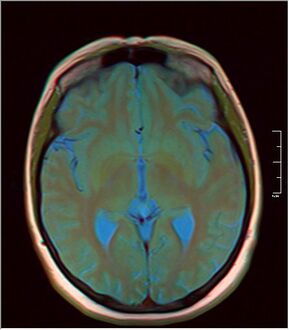

كيسة الغدة الصنوبرية pineal gland cyst هو تكيّس حميد (غير خبيث) في الغدة الصنوبرية، a small endocrine gland in the brain. Historically, these fluid-filled bodies appeared on 1-4% of magnetic resonance imaging (MRI) brain scans, but were more frequently diagnosed at death, seen in 4-11% of autopsies.[1] A 2007 study by Pu et al. found a frequency of 23% in brain scans (with a mean diameter of 4.3 mm).[1]

The National Organization for Rare Disorders states that pineal cysts larger than 5.0 mm are "rare findings" and are possibly symptomatic. If narrowing of the cerebral aqueduct occurs, many neurological symptoms may exist, including headaches, vertigo, nausea, muscle fasciculations, eye sensitivity, and ataxia. Continued monitoring of the cyst might be recommended to monitor its growth, and surgery may be necessary.[3]